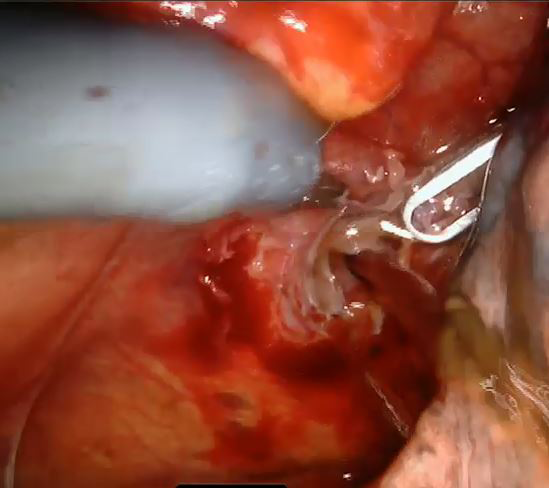

The pleural cavity was examined, and any pleural effusion was evacuated and sent for cytology. The pericardium and phrenic nerve were visualized and the distended pericardium was grasped with forceps and incised anterior to the phrenic nerve with scissors (Figure 1). A pericardial window was created (Figure 2), and the pericardium was sent for pathological evaluation as well as pericardial fluid was collected for cytological and microbiological analysis. A single thoracostomy tube was placed in pleural cavity and connected to underwater seal drainage. The insisions were closed in layers. All patients were transferred to intensive care unit for routine 24-hour postoperative evaluation and returned to ward. The thoracostomy tube was removed when the amount of daily drainage was below 100 mL.

Figure 1: The distended pericardium was grasped and prepared for incision by robotic instruments